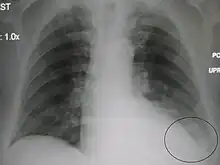

| A chest X-ray showing a very prominent wedge-shape bacterial pneumonia in the right lung | |

AP CXR showing left lower lobe pneumonia associated with a small left sided pleural effusion

AP CXR showing right lower lobe pneumonia

AP CXR showing pneumonia of the lingula of the left lung

Right upper lobe pneumonia as marked by the circle.

Left upper lobe pneumonia with a small pleural effusion.

Right lower lobe pneumonia as seen on a lateral CXR